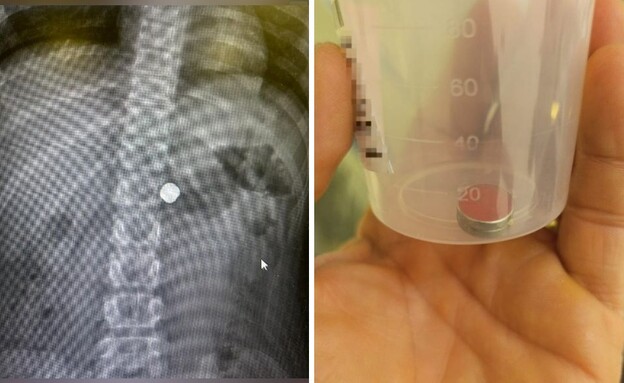

בלעה מגנטים

האב שמע את הילדה צועקת "בלעתי מגנט"

"בדקנו בעזרת צ'אט GPT מה צריך לעשות"